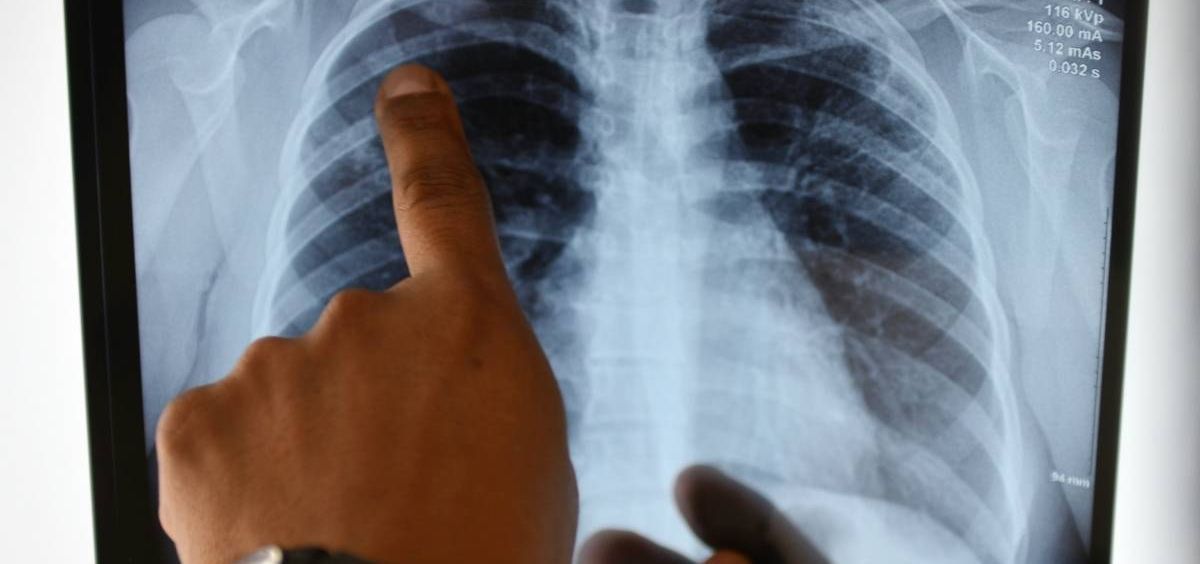

La Fundación Real Madrid y la compañía GSK han activado de nuevo la campaña de prevención del tabaquismo en la edad temprana a través del cuento 'No y punto porque #FumarNoMola', con motivo del Día Mundial contra la Enfermedad Pulmonar Obstructiva Crónica (EPOC).

Este año, además, se complementa con la realización de una activación específica para beneficiarios adultos, con el visionado del cortometraje 'La Bicicleta de Esther', producido por GSK y que refleja cómo es la vida de una enferma de EPOC, derivada del tabaquismo. Posteriormente, se producirá una breve charla sobre el documental entre los beneficiarios y el director de Patient Advocacy de GSK España, Esteban Palomo.